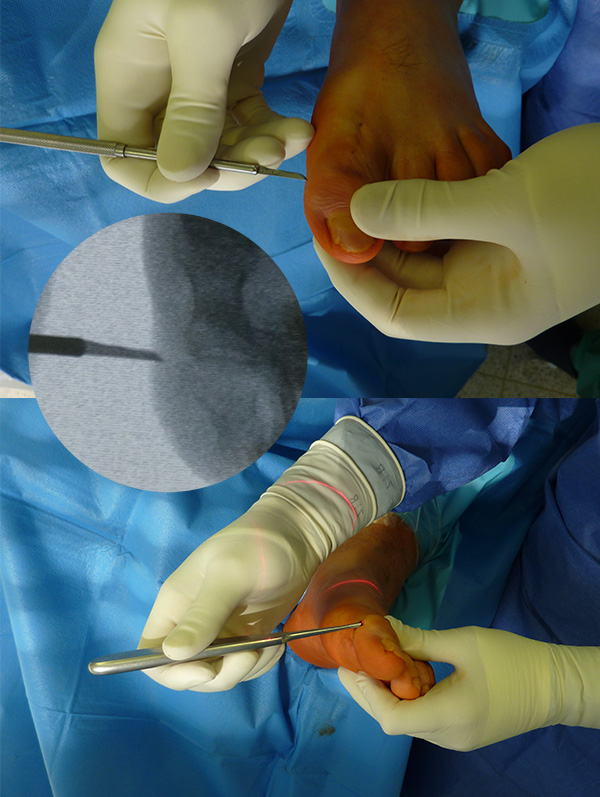

Zur Korrektur der Fehlstellung und zur Ulkus-Behandlung kann in minimalinvasiver Technik über ein mediales Portal eine Walzenfräse in das Interphalangealgelenk eingebracht werden. Über ein zweites laterales Portal wird nach Resektion der Gelenkflächen der Knochenabrieb ausgespült. Sobald ausreichend Knochen reseziert ist, kann die Zehe gestreckt werden. Die beiden abgetragenen Knochenflächen werden im Sinne einer IP-Arthrodese aufeinandergestellt. Es erfolgt dann die Transfixation der Arthrodese mittels ein bis zwei, über die Spitze der Endphalanx eingebrachten Zugschrauben. Problematisch ist es, wenn sich an dieser Stelle unverändert ein Ulkus befindet. In diesem Falle ist die Transfixation der Arthrodese mit zwei perkutan eingebrachten, schräg verlaufenden Kirschner-Drähten weniger risikoreich. Der Eintrittspunkt der K-Drähte befindet sich hier medial und lateral im Bereich der Endphalanx. Bei persistierender Fehlstellung kann je nach Vorspannung eine Tenotomie der EHL- und/oder der FHL-Sehne durchgeführt werden. Normalerweise entspannt sich die Sehne durch die Knochenresektion und den damit verbundenen Längenverlust ausreichend. Zur Korrektur der Fehlstellung „wird die Knochenlänge an die Sehnenlänge angepasst“.

Zum Lesen der Bildbeschreibung und zur Vollansicht bitte die Bilder anklicken.

Abbildung 5

Abbildung 6

Abbildung 7

Abbildung 8